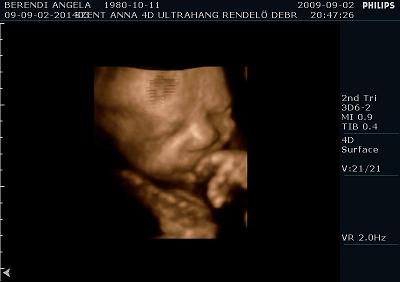

Ma voltunk UH-on. És a méretei alapján még mindig egy héttel idősebbnek nézik, de súlya tök normális 2350 gramm. Szóval azt mondják nem lesz akkora mint a kis Levi manó volt. Ennek azért örülök mert nagyobb az esély hogy meg tudom szülni, mivel nekem az első császár volt. Szóval drukkoljatok lányok!!